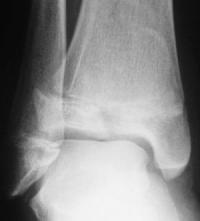

Les décollements épiphysaires Salter 3

- Trait de fracture passant par le cartilage de croissance et l’épiphyse

- Atteinte de la zone germinative du cartilage de croissance et fracture articulaire : risque d’épiphysiodèse et d’arthrose

- Diagnostic : radiographie de la cheville de face et de profil

- Forme particulière : la fracture de Tillaux. Elle touche l’enfant en fin de croissance suite à un traumatisme en rotation externe, alors que seule la partie antéro-interne du cartilage de croissance distal du tibia (zone d’insertion du ligament tibio-fibulaire antérieur) n’est pas encore fusionnée.

- Trait de fracture vertical dans le plan frontal, d’autant plus externe que la fin de croissance est proche.

- Exemple…